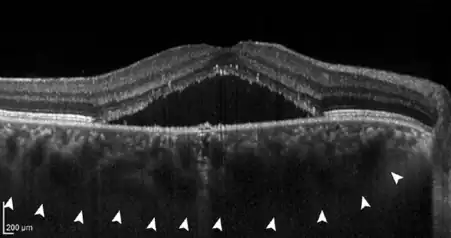

- If further damage to Bruch's membrane and the pigment epithelium causes fluid to accumulate under the retina, central serous chorioretinopathy (CSC) develops. In this stage, patients often have blurred vision and report a reduction in visual acuity with perception of a central "grey spot". In the majority of patients, spontaneous resolution of the subretinal fluid occurs within a few months, but recurs in up to 50% of cases. In some patients the fluid remains, making it a chronic disease; medical therapy or the application of various laser methods is possible.

- In about 25% of all patients with a chronic central serous chorioretinopathy, a proliferation of blood vessels from the choroid towards the retina can be detected (choroidal neovascularisation, CNV). CNV forms after an average of 17 years.[4] This stage is called pachychoroid neovasculopathy (PNV), [4] which can cause a massive reduction in vision due to bleeding and scarring of the macula.[5] Anti-VEGF therapy, which is injected directly into the eye (intravitreally), has proven to be an effective therapy in this case.